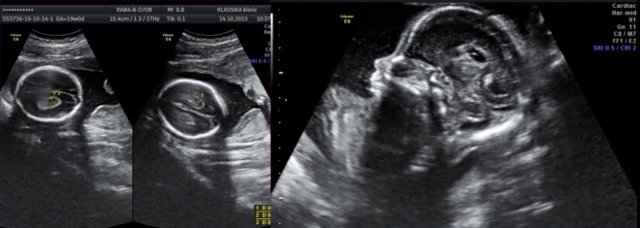

Сосудистые сплетения у плода образуются на сроке 18-19 недель. Именно в этот период, при проведении УЗИ могут быть обнаружены первые признаки кист, которые выглядят, как эхонегативные образования. Чаще всего в срок от 20 до 24 недель, когда идет активное формирование головного мозга, размер кисты уменьшается, и она полностью исчезает.

Для определения патологии проводится внутриутробное ультразвуковое обследования плода. Чаще всего лечение не требуется и, по мере развития нервной системы у плода, новообразования рассасываются.

Первые нарушения развития определяются ещё во внутриутробном периоде. Женщина проходит обязательные исследования. Благодаря ранним скринингам выявляют кисты сосудистых сплетений. Уже от 16 недель их можно контролировать с помощью повторной диагностики.

Проводится в период внутриутробного формирования. Это дает возможность установить наличие кистозной опухоли на начальных этапах ее формирования.